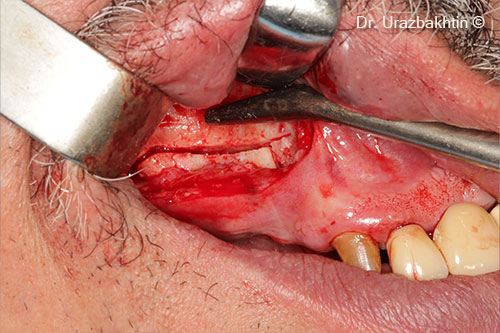

Osteotomy of the jaw ridge